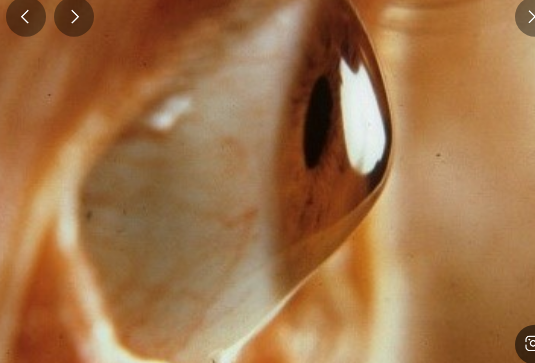

원추각막(keratoconus), 각막이 돌출된다고?

원추각막은 각막이 원뿔 모양으로 변형되어 발생하는 시력장애입니다. 각막은 눈의 앞부분을 덮고 있는 투명한 조직이며, 빛을 굴절시켜 망막에 상을 맺게 하는 역할을 합니다. 원추각막이 발생하면 각막이 비정상적으로 얇아지면서 돌출되어 부정난시가 발생하는 진행성 질환입니다.